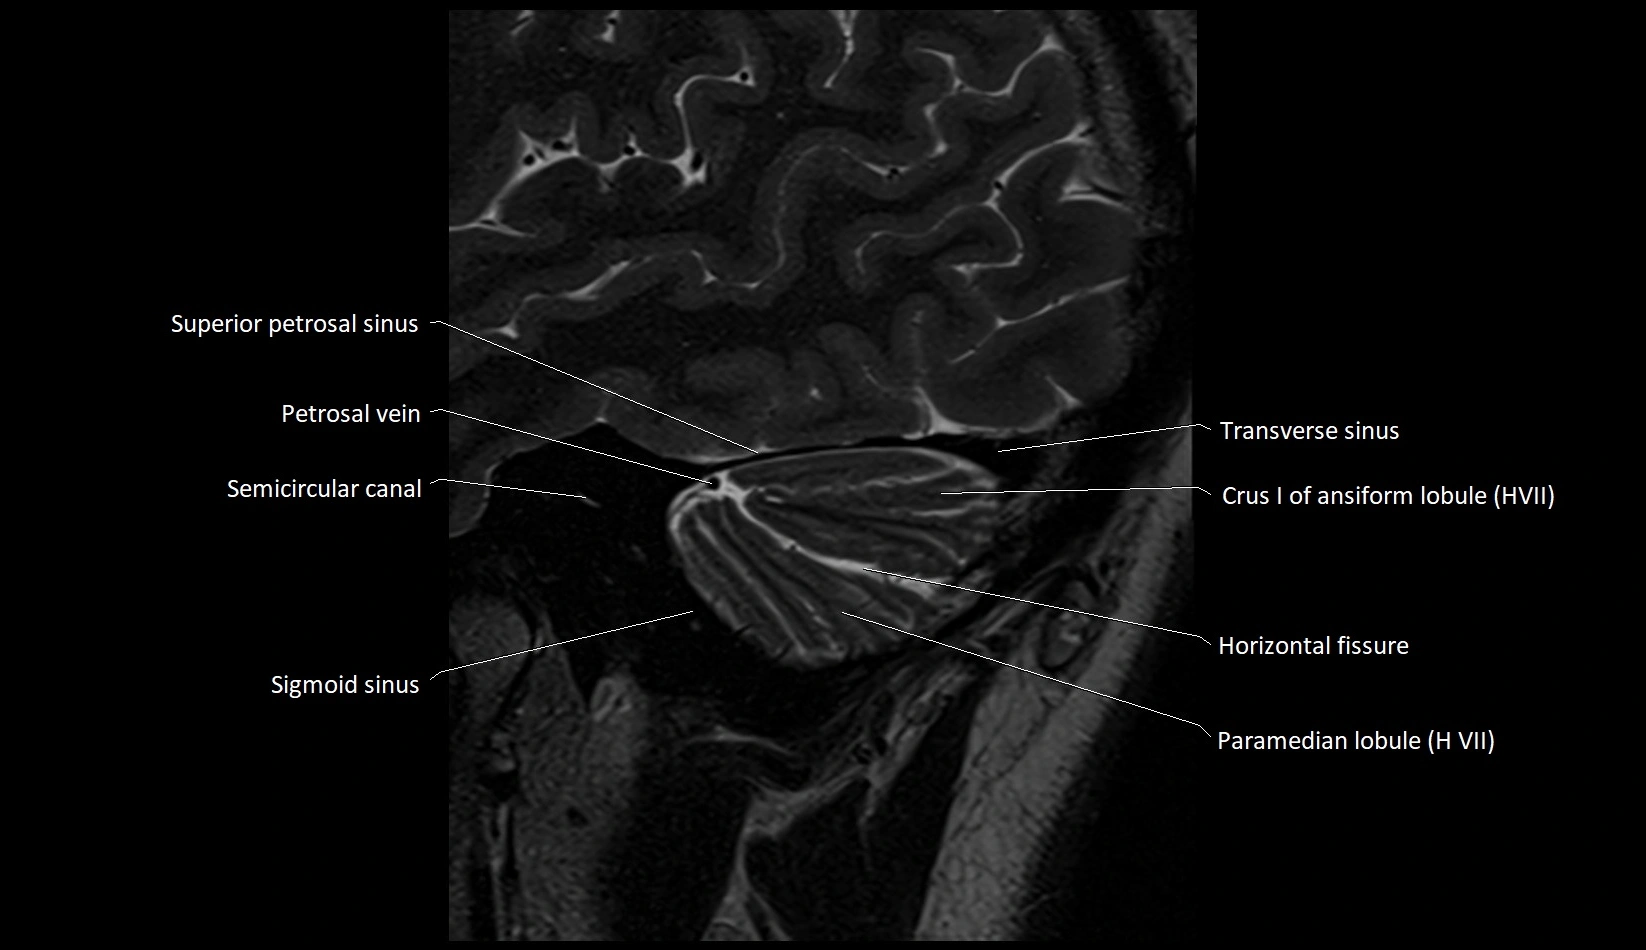

MRI images